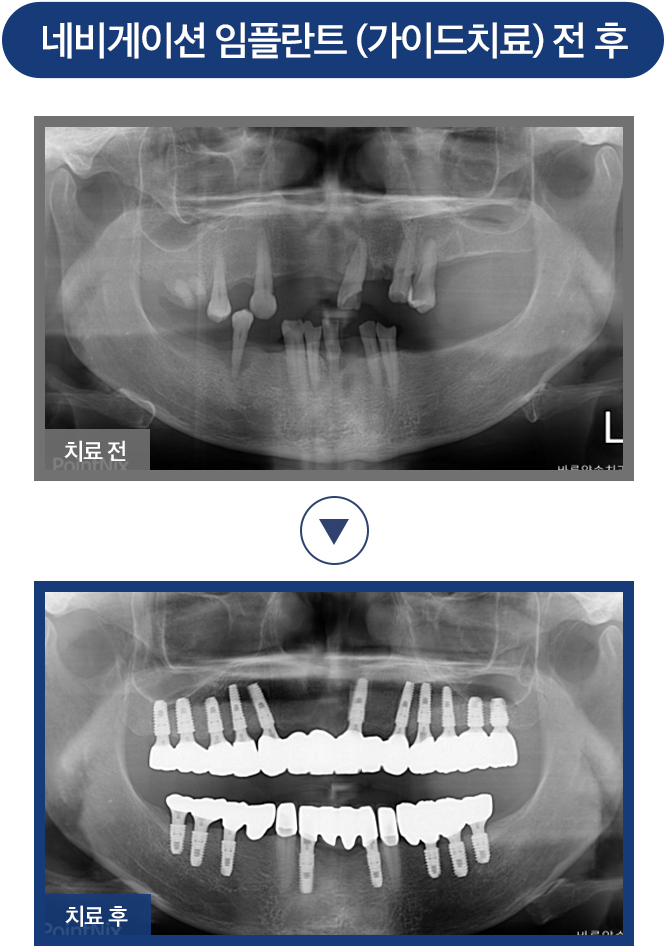

HOME · 디지털 임플란트 ·

치료전후사진

네비게이션 임플란트